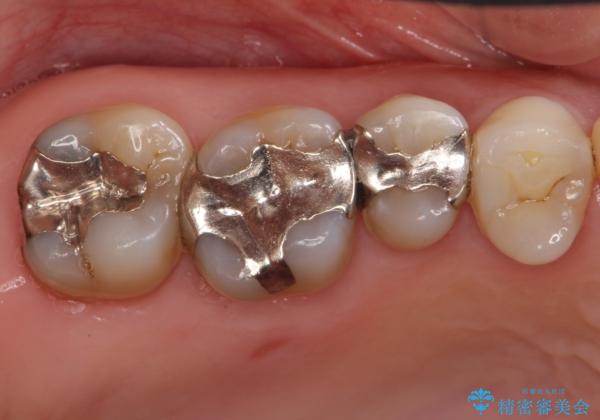

銀歯を白く 虫歯治療

- 虫歯治療を希望して来院。

保険適用の銀色のつめもののやり替えを行いました。

- 30.8万円(右上4567 emaxプレスインレー 7万円x4本)費用は治療当時の料金となります

自由診療のインレーの歯型には、シリコンを使用しています。また、処置時には8倍の拡大鏡を用いて、精密に治療しております。